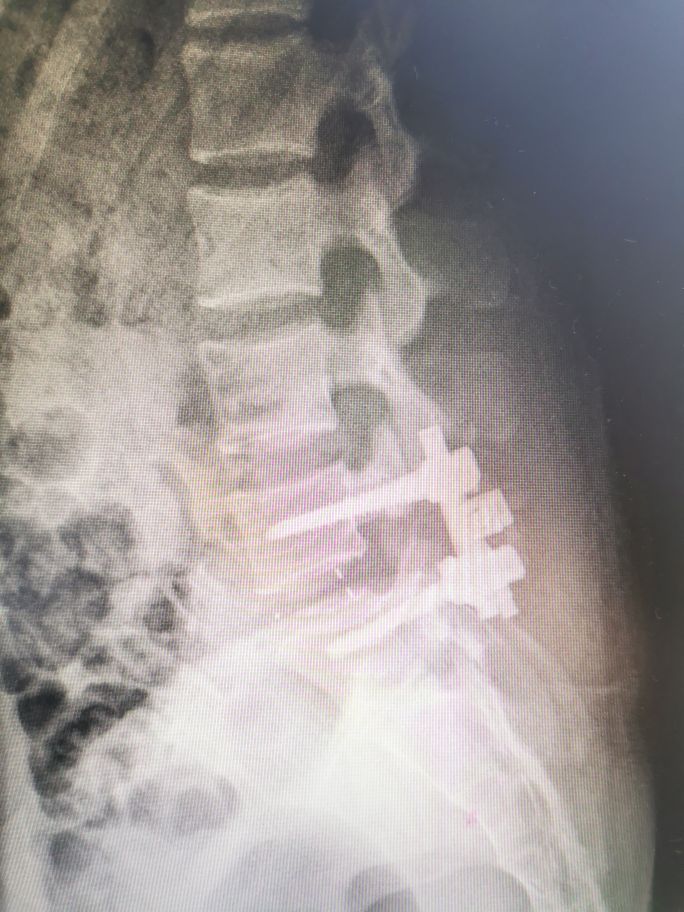

该患者住院后完善各项检查,全麻下行腰椎滑脱切开复位椎弓根螺钉内固定+植骨融合术,手术顺利,术后复查照片提示腰椎滑脱已经复位,术后三天抜引流管,术后五天佩戴支具下床活动,患者诉腰痛缓解。这是术后的照片:

大家看原来滑脱那里已经完全复位了,术后患者的疼痛也减轻了,最主要植骨融合以后腰椎就不会再出现滑脱了。